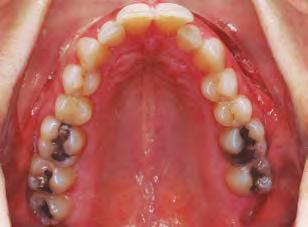

–Corticotomías y Ortodoncia. Ampliando límites del movimiento dental, por la Dra. Aranzazu Senosiain y cols. [50]

–Tratamiento de un caso de Ortodoncia y Cirugía Ortognática con placas preformadas y tecnología 3D, por la Dra. Elena Bonilla Morente y cols. [62]

–Uso del anclaje esqueletal como alternativa eficiente en el manejo ortopédico de clases III por deficiencia de maxilar superior, por el Dr. Carlos Becerra y cols. [74]

–MARPE, una alternativa a la disyunción en el paciente adulto, por el Dr. Enrique Solano y cols. [88]